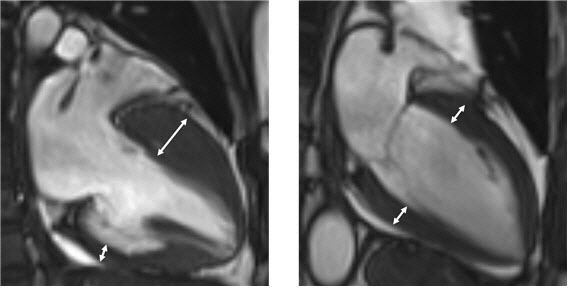

진단은 심장초음파, 자기공명영상 등 영상검사를 통해 이뤄지며, 비후된 심근 내에 섬유화가 진행돼 있거나 근육조직이 지방조직으로 변성이 돼 있는 상태가 관찰된다. 하지만 이 같은 조직변성이 없는 비후성 심근병증도 있는 만큼 전문의의 종합적 판단이 중요하다.